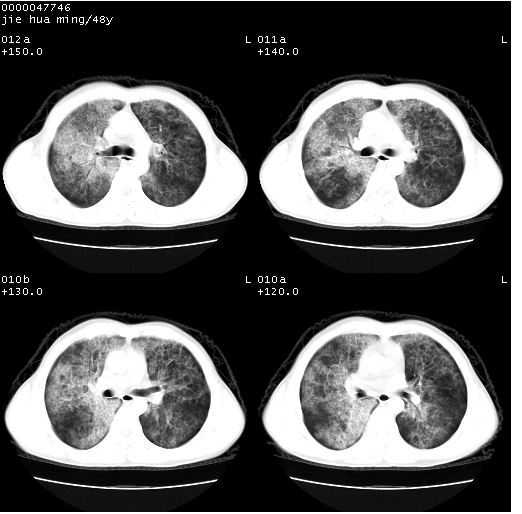

以下是引用dr.yang在2008-5-1 6:25:00的发言:[br]两肺广泛毛玻璃样的片状影,密度不均,边缘欠清,呈碎石路样改变,[br]考虑,1双肺间质性肺炎,2肺泡蛋白沉积症3支气管肺泡癌[br]

以下是引用hhcckk在2008-5-1 8:06:00的发言:[br]支持肺泡蛋白沉积症[br]依据:[br]1、病灶边缘清楚----地图征[br]2、病灶内部小叶间隔或小叶内间隔增厚所形成的网格状影----碎石路样表现[br]3、抗炎治疗无效(炎症抗炎治疗有效)[br]4、纵隔内未见肿大淋巴结(肺泡细胞癌时常有)[br][br]附肺泡蛋白沉积症资料[br][br]肺泡蛋白沉积症(pulmonary alveolar proteinosis)是一种原因不明的以肺泡腔内大量含脂糖蛋白样物质沉积为特征的疾病。[br]病理改变:(1)肺泡和细支气管腔内充满大量含脂糖蛋白样的粘稠物质,该物质为颗粒状或絮状的糖原pas染色阳性的磷脂蛋白。(2)肺泡壁及其间隔无异常改变。胸膜和淋巴结不受累及。(3)晚期可出现弥漫性肺间质纤维化。[br]临床表现:(1)好发年龄30~50岁,男性多于女性,偶见于儿童;(2)主要症状为呼吸困难、咳嗽、低热、消瘦、低氧血症和杵状指等。1/3的患者无症状。(3)实验室检查:痰液或肺泡灌洗液中可找到pas染色阳性颗粒物质。[br]hrct表现:肺泡蛋白沉积症具有特征性改变,即“碎石路样”表现(crazy-paving appearance,cpa)。主要包括(1)斑片状磨玻璃影:指肺野密度朦胧增加,内可见肺血管纹理影,系肺泡腔内充满低密度的磷脂蛋白物质所致。(2)其内部小叶间隔或小叶内间隔增厚所形成的网格状影,为小叶间隔水肿、肺泡壁内淋巴细胞和巨噬细胞浸润以及小叶内淋巴管扩张的缘故。(3)病灶边缘清楚,呈地图样分布于肺野外围或肺门及中央区。[br]

以下是引用zsl6918在2008-5-1 7:35:00的发言:[br]双肺磨玻璃样病变,可见铺碎路石征,病变区与正常区交错。边界清晰。符合肺泡蛋白质沉着征,高分辨扫描会更清楚漂亮。建议临床肺泡灌洗。

以下是引用yangyudong333在2008-5-1 5:36:00的发言:[br][br] 两肺广泛毛玻璃样的片状影,密度不均,边缘欠清,呈碎石路样改变,[br]考虑,1双肺间质性肺炎,2肺泡蛋白沉积症[br]